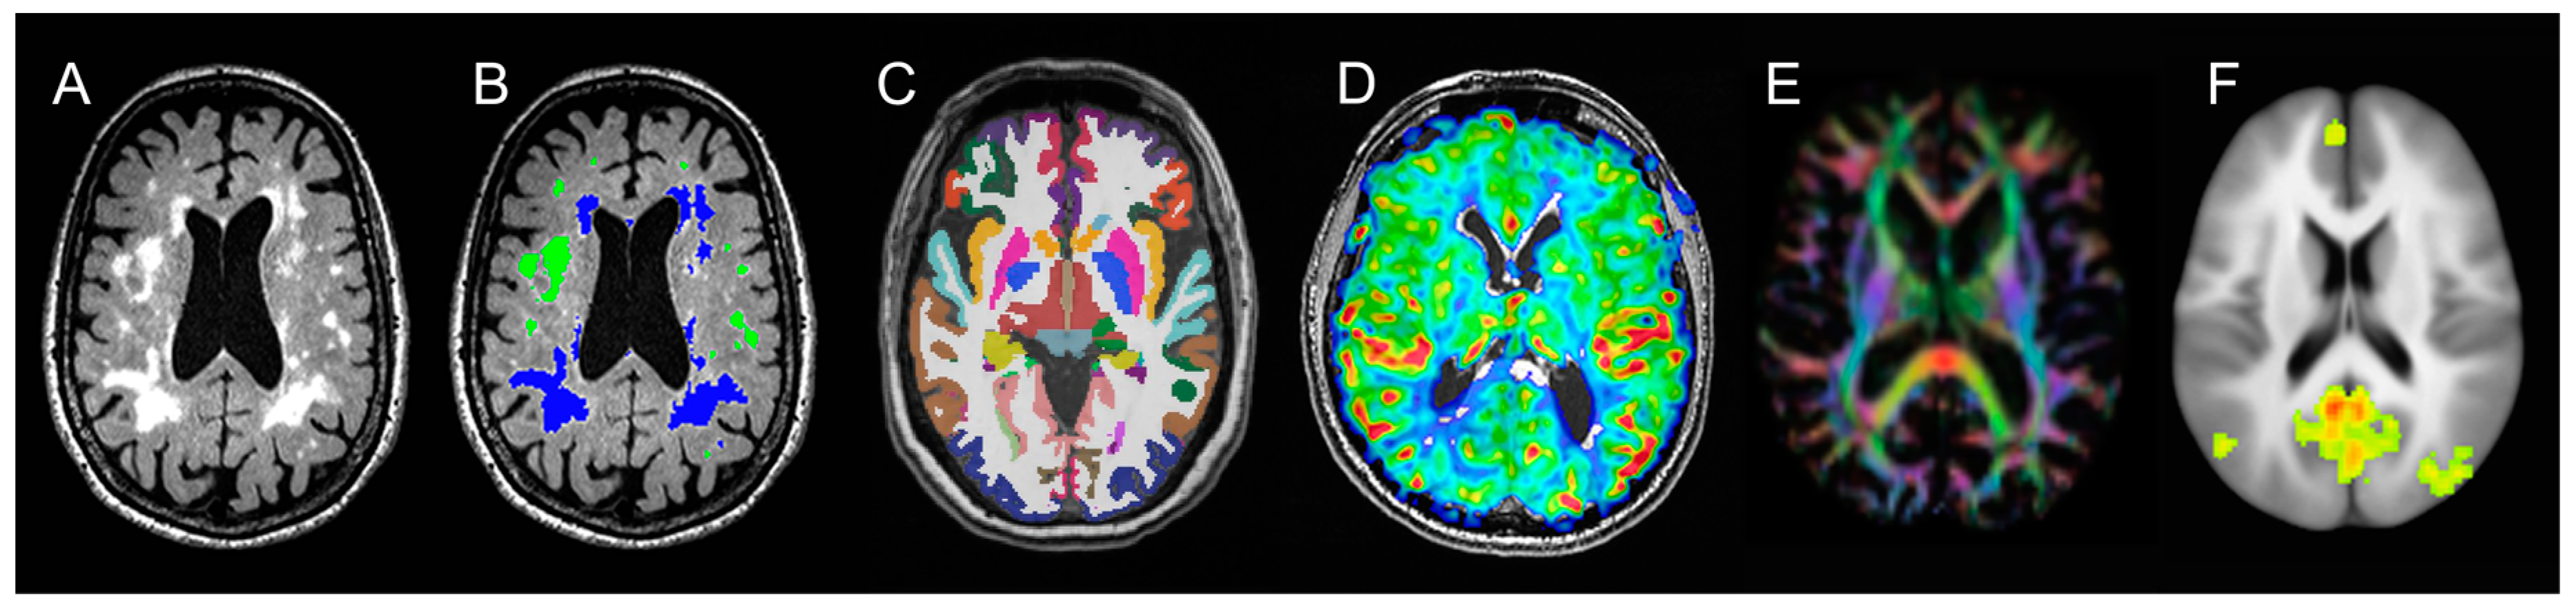

2.4.1. Neuroimaging